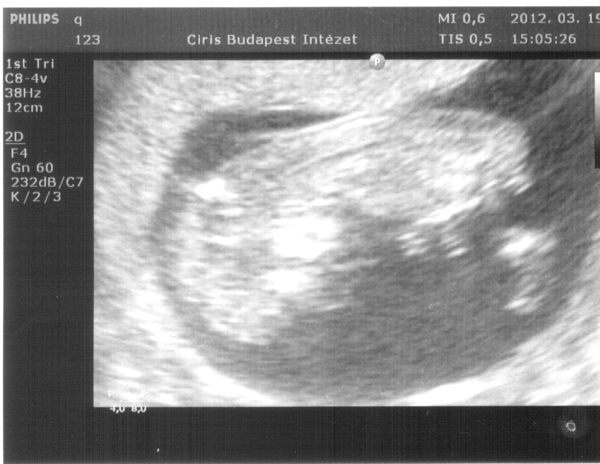

Ja Suti vicces, mert az en ferjem akarja az ikreket nagyon, es egy honapja mondom neki, hogy nem lesznek ikrek ,mert csak egy petesejt erik spontan ciklusban, erre kijovok es mondom neki, hogy kepzeld ketto is erik. O meg: na ugye hogy megmondtam, hogy ikreim lesznek. Bolond ember na